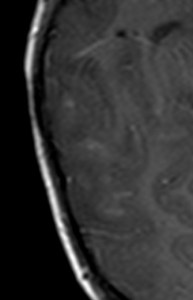

- Secuencias potenciadas en T2 y FLAIR muestran lesiones hiperintensas, de afectación bilateral, irregular, mal definidas, de tamaño variable y asimétricas que son la expresión de áreas de inflamación y desmielinización de la sustancia blanca. Las lesiones afectan sobre todo a la sustancia blanca cerebral, pero también a la sustancia gris y núcleos de la base y a médula espinal.

Las localizaciones cerebrales más frecuentemente afectadas son la sustancia blanca profunda (frontal y parietal sobre todo), sustancia blanca yuxtacortical, sustancia blanca periventricular, cuerpo calloso, sustancia gris cortical, tronco del encéfalo y cerebelo.